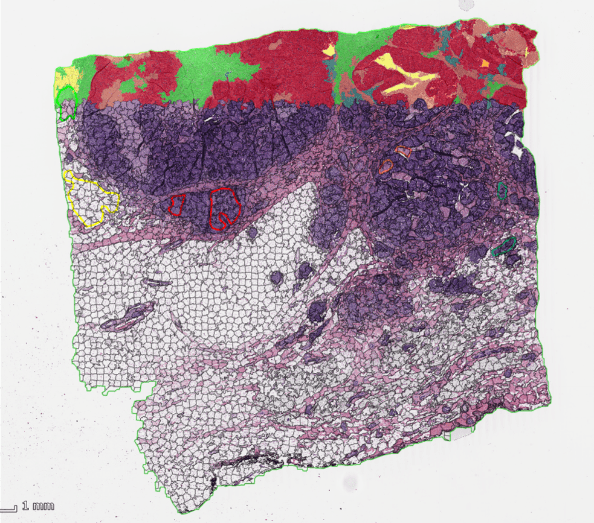

MICAIA_Monitor_heatmap

释放MIKAIA®️(米康雅®️)工作室APP的力量

该应用程序对细胞类型之间进行空间分析。它将样本解释为一个图行,其中细胞是节点,细胞与细胞间的连接是边缘。每个细胞与相邻的连接在一起。然后对相邻的两种细胞类型进行连接分类。根据需要,可以通过提供最大距离的完全切断或基于连接细胞的平均长度和标准偏差来过滤长连接。最后,将连接细胞绘制为矩形图并显示在矩阵表中,其中每个列和行对应于一个源和目标细胞类型。

细胞对细胞连接分析

人工智能创作